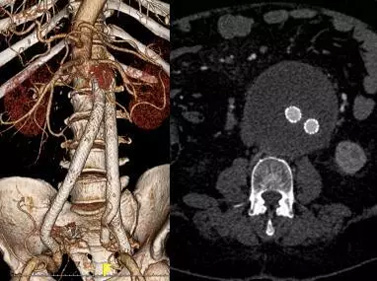

向家属简要讲明病情危重性及目前治疗方案的可选项(开放手术治疗及腔内“三明治”保留分支微创治疗),急症行腹主动脉瘤腔内修复+右髂内动脉栓塞+三明治重建左髂内动脉。术后患者动脉瘤完全隔绝,转危为安,如下面图片所示: